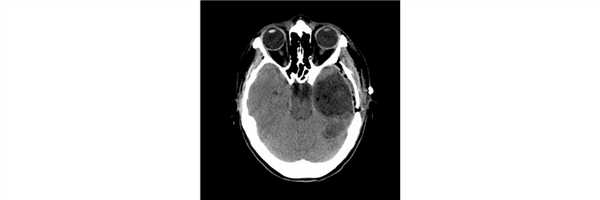

Пациент 38 лет дважды оперирован по месту жительства по поводу опухоли правой теменно-затылочной области, выполнена резекционная трепанация черепа (гистологический диагноз - SEGA - субэпендимарная гигантоклеточная астроцитома). Вторая операция осложнилась развитием раневой ликвореи и менингита. Дефект черепа не закрыт. Адъювантная терапия не проводилась. При контрольной МРТ картина рецидива опухоли с крупным кистозным и солидным компонентом.

Проведена операция - микрохирургическое удаление опухоли правой теменно-затылочной области с использованием нейрофизиологического мониторинга

Послеоперационный период протекал без осложнений. При контрольной СКТ картина радикального удаления опухоли.

Гистологический диагноз - морфологическая картина, иммунофенотип и данные молекулярно-генетического исследования в большей степени соответствуют анапластической плеоморфной ксантоастроцитоме, WHO Grade III, BRAF-мутантной. Рекомендуется предоставить препараты от первых операций.

В препаратах от предыдущих операций идентичная преимущественно веретеноклеточная опухоль с участками выраженного полиморфизма ядер и клеток. Проведено сравнение препаратов предыдущих операций с препаратами от настоящего вмешательства - картина опухолей идентична и соответствует анапластической плеоморфной ксантоастроцитоме.

Пациент после выписки направлен на проведение адъювантной терапии (в т.ч. тартегтной терапии).